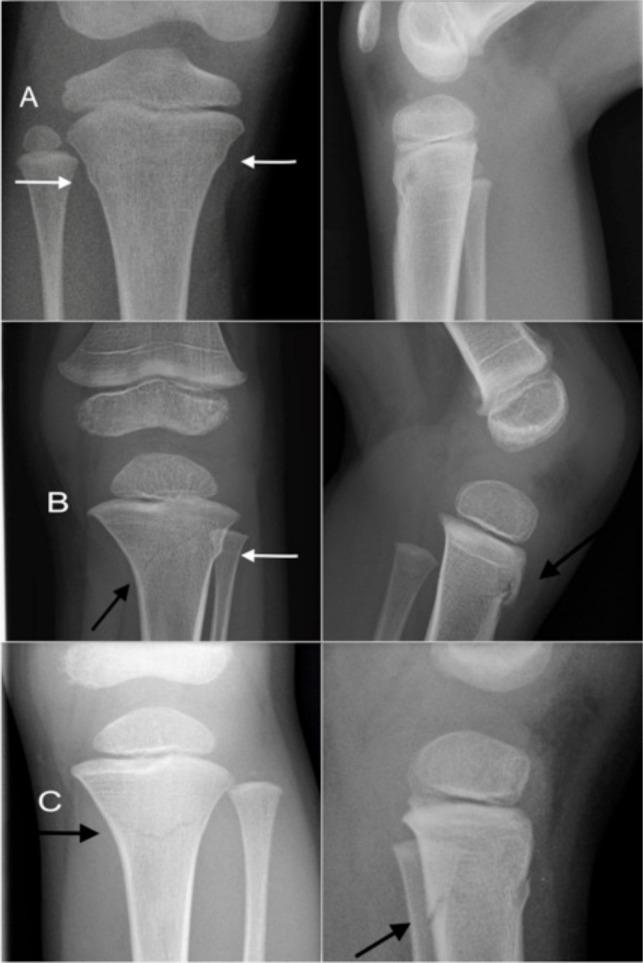

All children, aged < 16 years, who had suffered from proximal tibia fracture in Oulu Arc and Oulu between 2006 and 2017 were enrolled (n = 101). Their annual incidence was determined using the official population-at-risk, obtained from the Statistics Finland. The specific characteristics and risk factors of the patients and their fractures were evaluated. Radiographic findings were analyzed, in particular the anterior tilting of the proximal growth plate, due to impaction.

The annual incidence increased two-fold from 9.5 per 100 000 children (2006 to 2009) to 22.0 per 100 000 (2014 to 2017) (difference: 12.5; 95% confidence interval 5.1 to 20.3 per 100 000; p = 0.0008). The mean annual incidence of trampoline impaction leg fractures was 15.4 per 100 000 children. In 80% of the cases multiple children had been jumping together on the trampoline. Anterior tilting (mean 7.3°, SD 2.5°, 6.1° to 19.1°) ) of the proximal tibial plate was seen in 68.3% of the patients. Satisfactory bone union was found in 92.7% during follow-up. Isolated patients presented delayed bone healing.

The incidence of trampoline leg fractures has increased 130% during the 12 years of the study period. Many of these injuries could have been prevented by avoiding having several jumpers on the trampoline at the same time. Anterior tilting of the growth plate was a common finding and should be recognized in the primary radiographs.